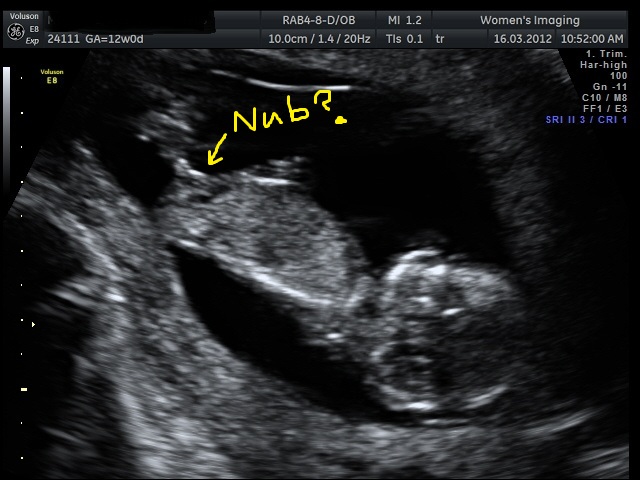

Attachment 3519

Sorry upside down.....Attachment 3520

Maybe not...that's a pretty big bulb at the end of the nub.

BOY!!!!! :D

My guess would be boy, too! Good luck!! :)

I think Boy too! GL

What gestation exactly was this taken at? If around the 12 week mark I could see it going either way. If around 13 weeks, I would lean girl. Either way its not a totally clear nub that screams one or the other in my opinion.

The u/s was at about 12weeks 3days, according to measurements. By lmp 12weeks 5 days

I think boy too! The end of the nub is so rounded, not forked like a girl nub. Hope you get your healthy boy! Please make sure to update!!!

Thanks......the more i think about it the more i think girl. But its a completely different looking nub to that of my 2nd DD; hers was 100% girl at the same gestation.